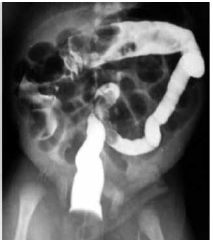

Recém-nascido, com três dias de vida, apresentou distensão abdominal com piora progressiva e dois episódios de vômitos amarelados. Eliminou pequena quantidade de mecônio algumas horas antes da avaliação clínica. AP: nascido a termo, filho de mãe diabética. Examefísico: bom estado geral, hidratado, abdome distendido globalmente, sem sinais de reatividade peritoneal.

Raio-X de abdome com distensão gasosa difusa em intestino delgado. Enema opaco com contraste hidrossolúvel, conforme imagem a seguir:

Após a realização do enema opaco, houve eliminação de grande quantidade de mecônio, com melhora da distensão abdominal. Não houve novos episódios de vômitos, e o paciente apresentou boa aceitação de dieta e evacuações diárias. Atualmente, com vinte dias de vida, o paciente mostra-se assintomático.

A principal hipótese diagnóstica para o quadro apresentado nos primeiros dias de vida é